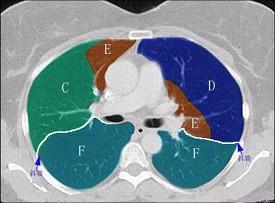

结合肺段模式肺动脉干与右肺动脉层面(见图),选出右肺中叶的组成 ( )A、D+EB、D+E+FC、B+CD、B+C+DE、B

问题 结合肺段模式肺动脉干与右肺动脉层面(见图),选出右肺中叶的组成 ( )

选项 A、D+E B、D+E+F C、B+C D、B+C+D E、B

答案 A